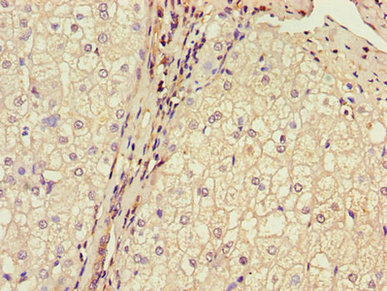

Immunohistochemistry of paraffin-embedded human gastric cancer using CSB-PA002816LA01HU at dilution of 1:100